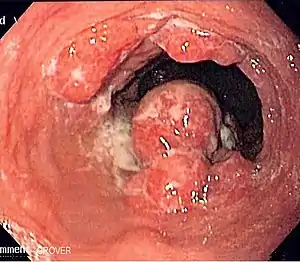

![]() | |

| Endoscopic image of an esophageal adenocarcinoma | |

Although an occlusive tumor may be suspected on a barium swallow or barium meal, the diagnosis is best made with an examination using an endoscope. This involves the passing of a flexible tube with a light and camera down the esophagus and examining the wall, and is called an esophagogastroduodenoscopy. Biopsies taken of suspicious lesions are then examined histologically for signs of malignancy.